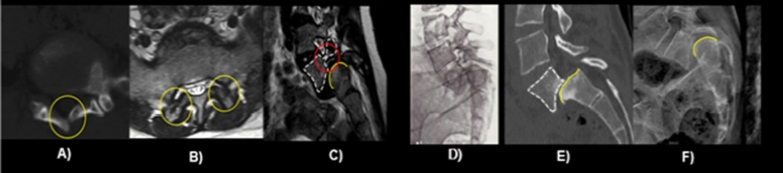

Fig. 1.

A schisis of L5 and S1 laminae, B sagittal orientation of articular facets, C L5 pedicle hypoplasia, D slippage of the L5 vertebral body, E trapezoidal L5 body, F rounded sacral dome